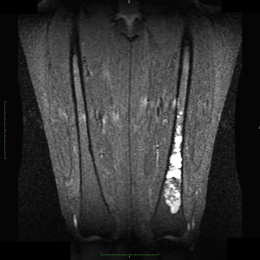

Radiographic imaging is used to help form a diagnosis. These include X-Ray, MRI, CT and Bone Scans

An example of an MRI is shown.